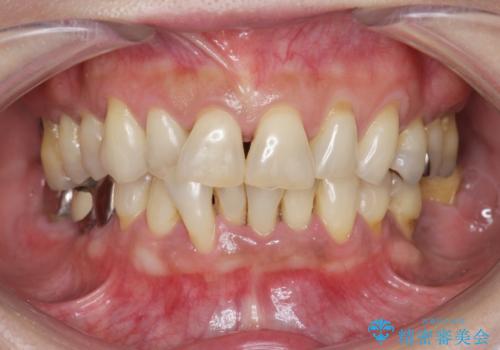

総合歯科治療 → 歯周病治療&矯正歯科治療

- 歯周病 、インプラント、 矯正 全顎治療- 担当医 大元洋佑